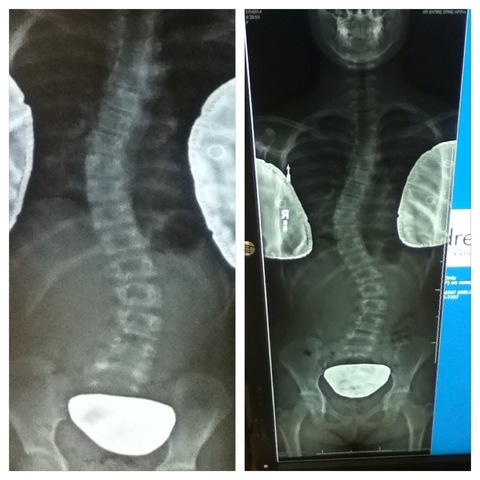

Back Brace

I got my back brace over a year and a half ago. I have scoliosis, to prevent my curves getting worse, I have to wear my brace about 23 hours a day.